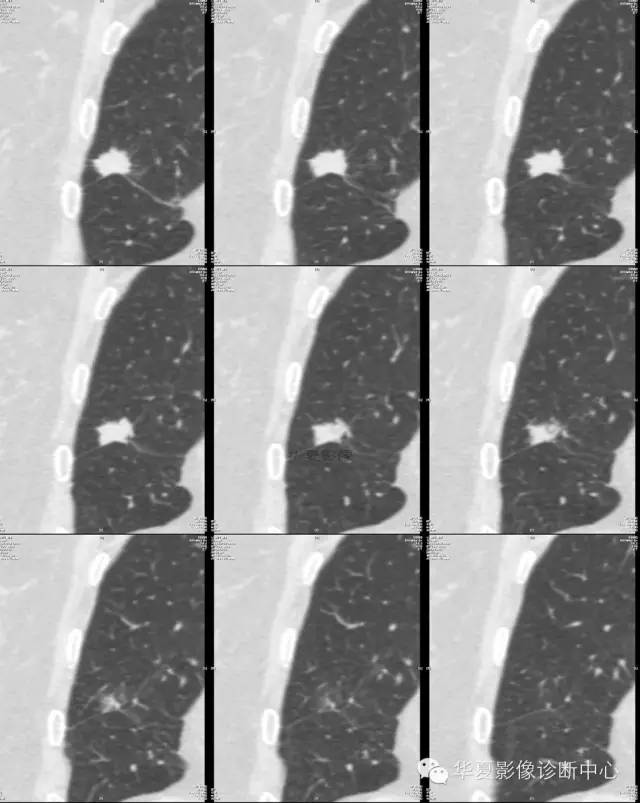

【病例学习】典型周围型肺癌CT病例一例

女,56岁,其父因肺癌去世,自觉胸部疼痛不适来诊要求拍胸片。